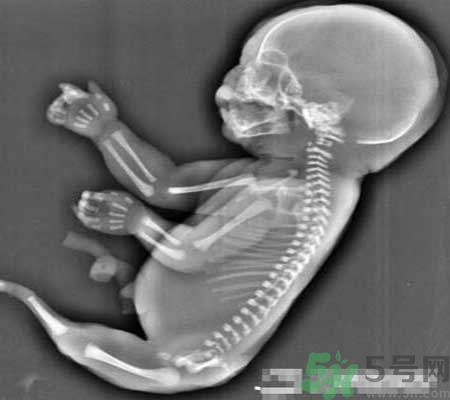

當(dāng)時經(jīng)超聲檢查發(fā)現(xiàn),孕婦宮腔內(nèi)未見羊水暗區(qū),借助胎兒骨骼影像順序連續(xù)掃查,發(fā)現(xiàn)胎兒頭顱、胸腔、雙上肢,也可以看到一個跳動的心臟。但下肢只找到一條股骨,未見雙腿、膀胱,只有一側(cè)發(fā)育不良的腎臟。